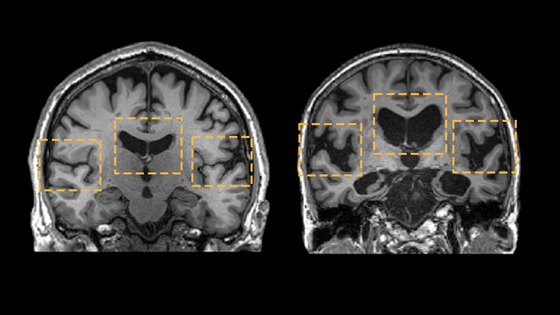

중년을 어떻게 보내느냐에 따라 당신의 뇌는 치매에 부쩍 다가설 수도 있고, 한없이 미룰 수도 있다. 치매 관리의 핵심 시기는 중년이다. 부피가 충분해 보이는 오른쪽 뇌는 정상인. 쪼그라들어 휑해 보이는 왼쪽 뇌는 알츠하이머 환자. 사진 Leonidas Chouliaras et al., 2023